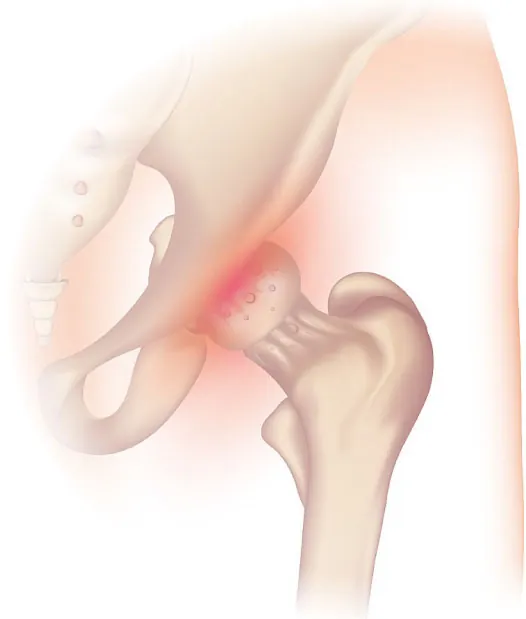

Diagram showing osteoarthritis of the hip joint

Figure 13.6 Osteoarthritis of the hip joint involves the wearing down of the joint cartilage over time, causing pain. (credit: Hip Osteoarthritis by Injurymap/Wikimedia Commons, CC BY 4.0)